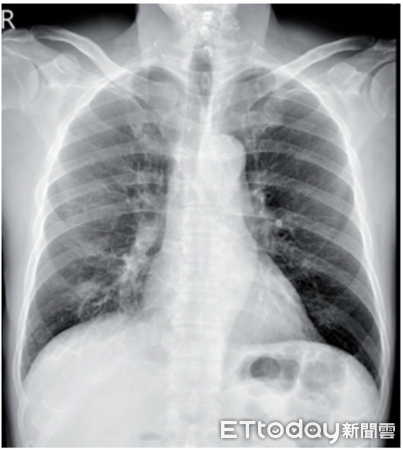

▲男子肺部有持續長大腫塊,且長期咳嗽,經切片證實非癌症,而是球黴菌感染。圖非當事人。(圖/資料照)

▲張先生肺部影像,右下出現陰影。(圖/中醫大附醫提供,下同)

陳昫元指出,張先生讓醫療團隊更警覺的是影像變化,因為根據胸部電腦斷層,他右下肺葉的結節在2年間由0.8公分長至1.9公分,且邊緣不規則,並合併淋巴結腫大,種種徵象確實類似肺癌。

陳昫元指出,球黴菌症在X光、電腦斷層上,常呈現不規則結節或腫塊,症狀也可能有慢性咳嗽、發燒、夜間盜汗與體重減輕,故若未主動提及旅遊史,極易誤判為肺癌或肺結核;值得一提的是,球黴菌症不會人傳人,患者無須隔離,接受正確治療即可。